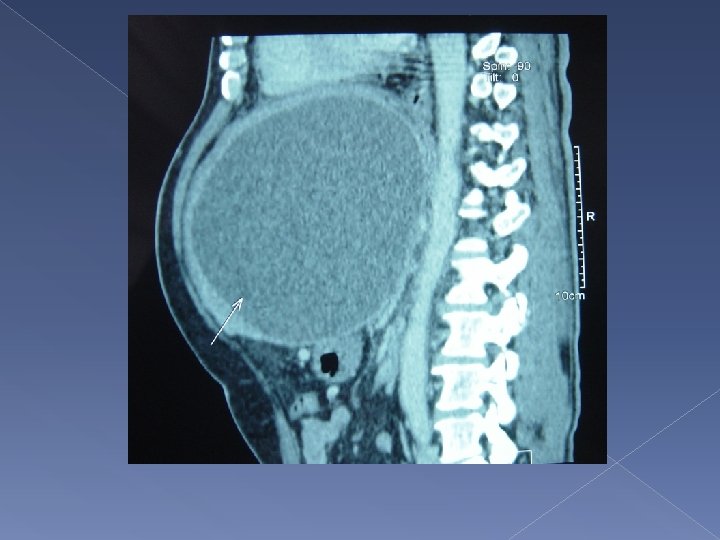

Blood tests - Bilirubin 16, ALP 133 - CEA 0. 5, AFP 3 HBs. Ag and anti- HCV : Negative CT abdomen with contrast was performed

19 cm huge thick walled cystic lesion arising from left liver